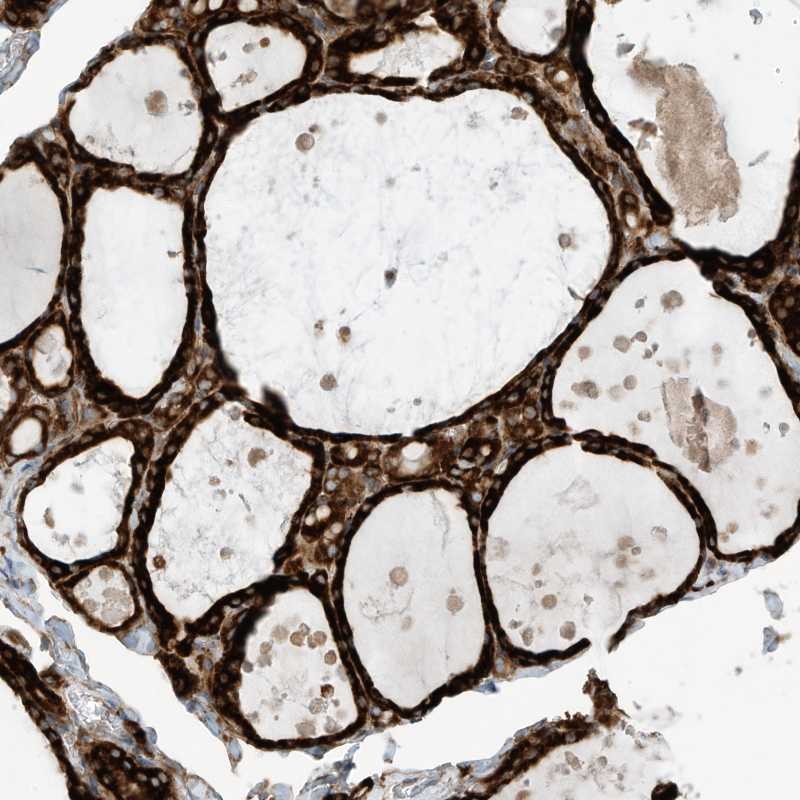

Immunohistochemical staining of human thyroid gland shows strong cytoplasmic positivity in glandular cells.